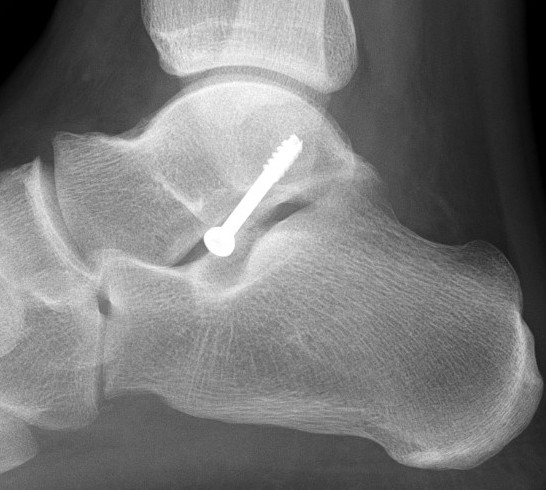

Operative Management

Indications

Large / displaced fragments

Intra-articular fracture with risk of subtalar OA

Options

1. ORIF - headless compression screw

2. Excision

Approach

Direct lateral approach to the talus

- lateral malleolus to base 4th metatarsal

- between peroneal tendons and extensor tendons

- can use image intensifier to mark incision

- excise fat over subtalar joint